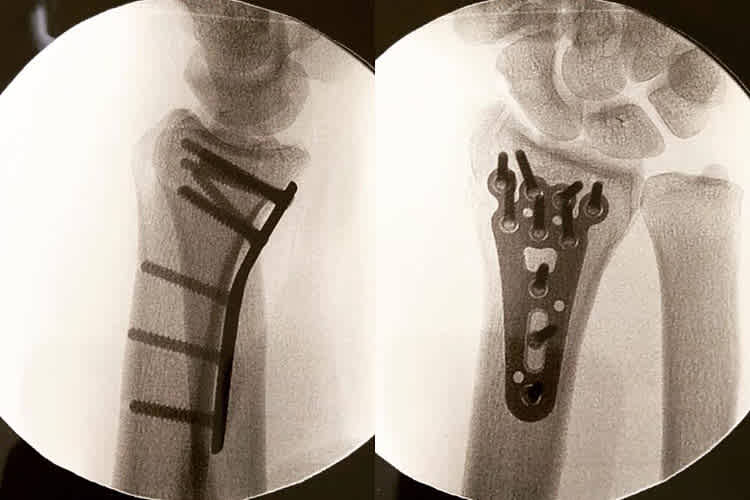

"Es war ein schlimmer Unfall. Ich habe mich mehrfach überschlagen und bin immer wieder auf Kopf, Beinen, Kopf, Beinen gelandet. Ich kann mich gar nicht erinnern, wann ich mich das letzte Mal derart oft überschlagen habe. Mein X-lite Helm, meine iXS-Kombi und die Daytona-Stiefel haben mich vor schlimmeren Verletzungen bewahrt", stellte Saiger, der sich unmittelbar danach auf die Heimreise in seine Wahlheimat Liechtenstein machte, fest. Im Kantonsspital von St. Gallen wurde Saiger nochmals einer genauen Untersuchung unterzogen. Die Erstdiagnose wurde von den Ärzten bestätigt. Ich werde noch am Montag operiert. Das bedeutend, dass jetzt einige Wochen Pause anstehen. Meine Teilnahme am North West 200 und der Tourist Trophy fallen damit natürlich auch flach. Neben der herben Enttäuschung ist es auch ein finanzieller Schlag für mich. Die letzten sechs Wochen habe ich wie ein Tier dafür gearbeitet." Nur einen Tag nach dem Eingriff, bei dem das linke Handgelenk mit einer Platte und Schrauben stabilisiert wurde, postete der für seine Späße gegenüber seinen Rennfahrerkollegen bekannte Steirer auf seiner Facebook-Seite ein Röntgenbild mit folgendem Kommentar: "Operation erledigt. Danke ans Kantonsspital St. Gallen für die super Arbeit! Morgen früh geht’s ab zur NW200, leider nur als Zuschauer und natürlich um meine Fantrip-Reisenden zu begleiten!"